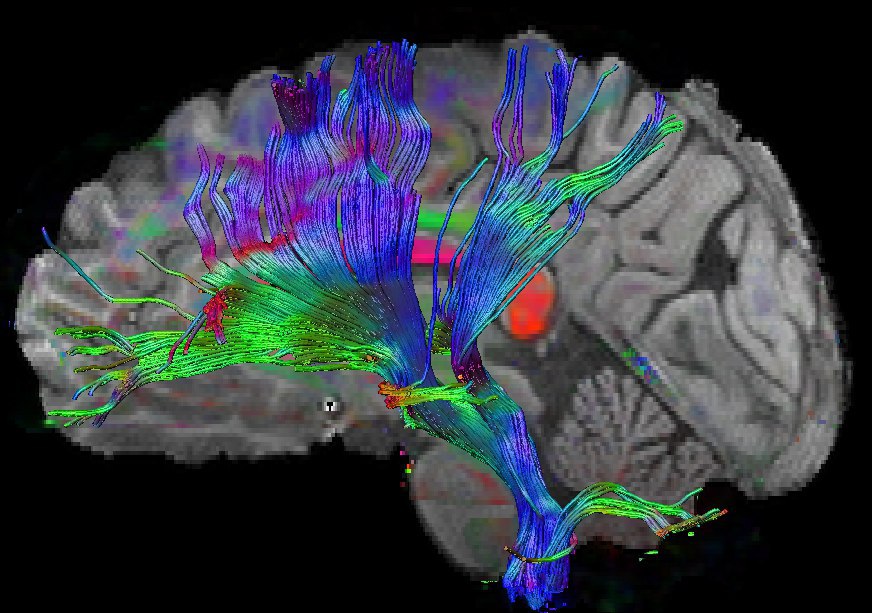

Коннектом мозга: визуализация связей и нейронных путей